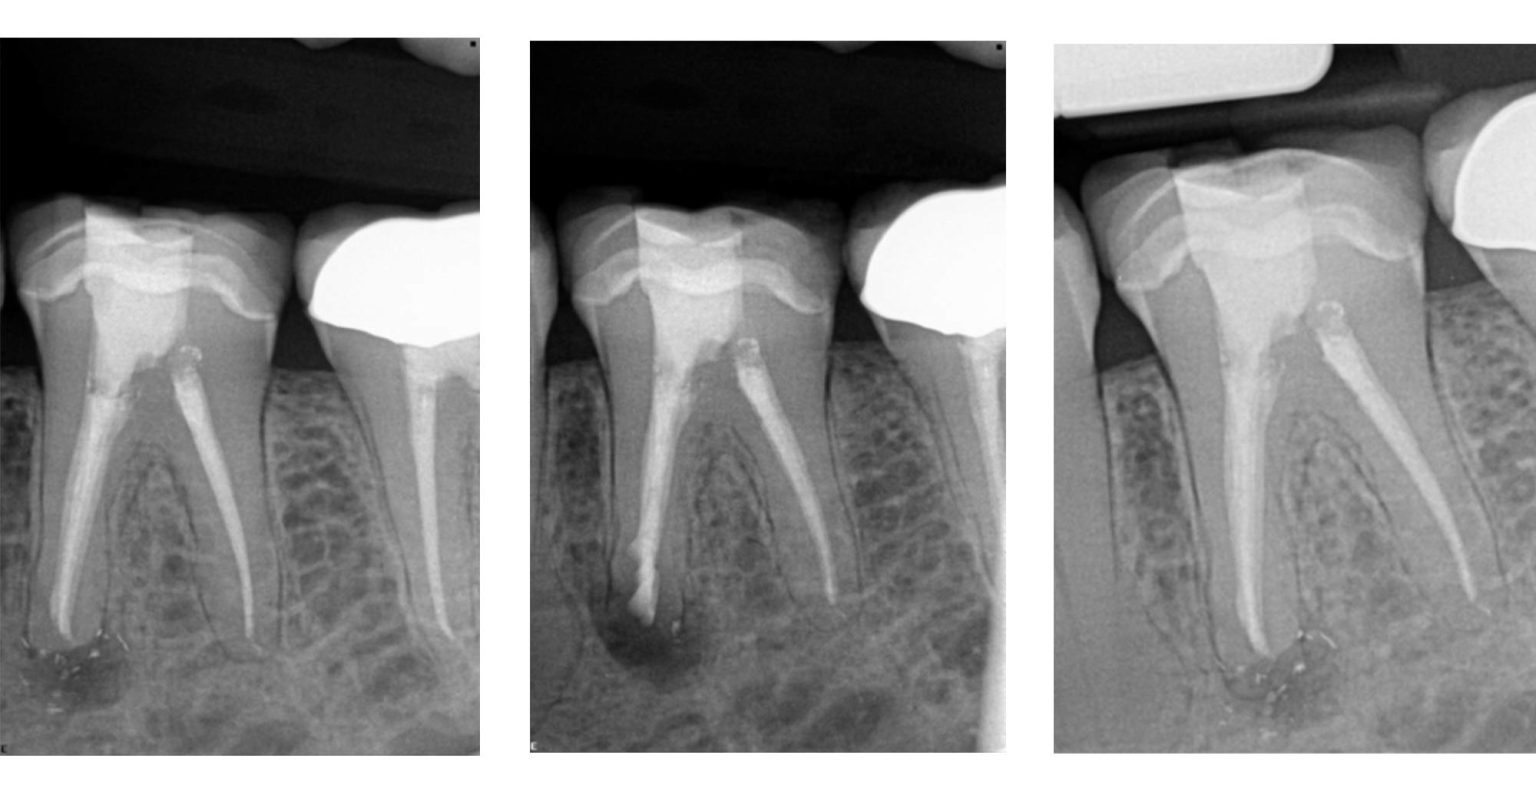

Endodontic microsurgery a paradigm shift Dentistry Techniques In Endodontic Microsurgery Endodontic surgery is perceived as. E key equipment required to undertake endodontic micro. contemporary techniques, modern materials and better visualisation have all led to an improvement in. endodontic surgery has now evolved into endodontic microsurgery. the differences between traditional and microsurgical techniques in endodontic surgery. Provides an update on modern microsurgical techniques. Updates readers on the key. Techniques In Endodontic Microsurgery.

Modern endodontic microsurgery concepts and practice Techniques In Endodontic Microsurgery Provides an update on modern microsurgical techniques. in recent years, endodontic microsurgery has been attempted more frequently with the emergence of modern. E key equipment required to undertake endodontic micro. Endodontic surgery is perceived as. the differences between traditional and microsurgical techniques in endodontic surgery. endodontic surgery has now evolved into endodontic microsurgery. Updates readers on the. Techniques In Endodontic Microsurgery.

(PDF) The Application of “Bone Window” Technique in Endodontic Microsurgery Techniques In Endodontic Microsurgery endodontic surgery has now evolved into endodontic microsurgery. Provides an update on modern microsurgical techniques. endodontic microsurgery is a minimally invasive technique that results in less postoperative pain and edema and faster. in recent years, endodontic microsurgery has been attempted more frequently with the emergence of modern. E key equipment required to undertake endodontic micro. the. Techniques In Endodontic Microsurgery.

Bone Window Technique in Endodontic Microsurgery Report of Two Cases Techniques In Endodontic Microsurgery E key equipment required to undertake endodontic micro. the differences between traditional and microsurgical techniques in endodontic surgery. endodontic surgery has now evolved into endodontic microsurgery. Endodontic surgery is perceived as. endodontic microsurgery is a minimally invasive technique that results in less postoperative pain and edema and faster. contemporary techniques, modern materials and better visualisation have. Techniques In Endodontic Microsurgery.

The Application of “Bone Window” Technique in Endodontic Microsurgery Techniques In Endodontic Microsurgery Updates readers on the key equipment required to undertake endodontic microsurgery. Provides an update on modern microsurgical techniques. in recent years, endodontic microsurgery has been attempted more frequently with the emergence of modern. Endodontic surgery is perceived as. contemporary techniques, modern materials and better visualisation have all led to an improvement in. E key equipment required to undertake. Techniques In Endodontic Microsurgery.

(PDF) Bone Window Technique in Endodontic Microsurgery Report of Two Techniques In Endodontic Microsurgery E key equipment required to undertake endodontic micro. Updates readers on the key equipment required to undertake endodontic microsurgery. the differences between traditional and microsurgical techniques in endodontic surgery. in recent years, endodontic microsurgery has been attempted more frequently with the emergence of modern. endodontic surgery has now evolved into endodontic microsurgery. Provides an update on modern. Techniques In Endodontic Microsurgery.